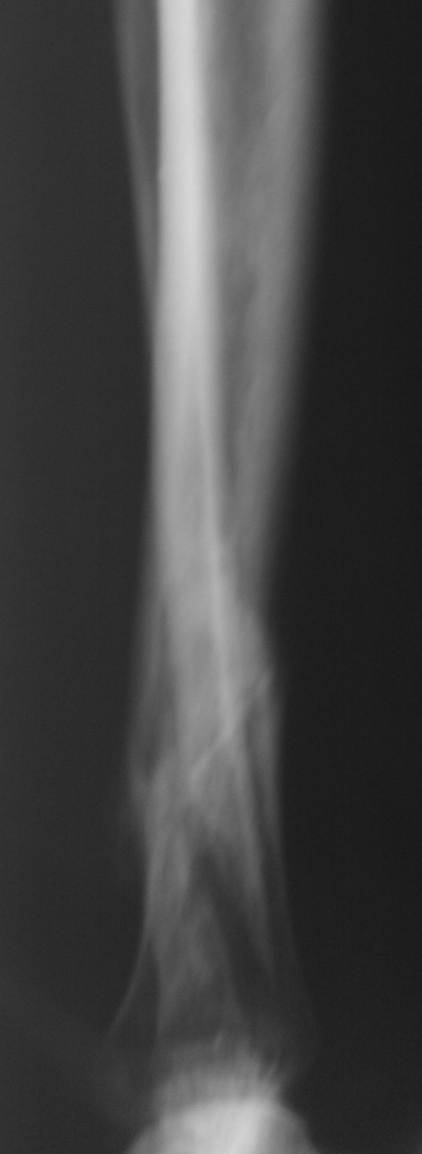

пример функционального лечения по Сармиенто похожего перелома.

Рентгенограммы в 1 мес, 3,5 мес, фото  и видео 3,5 мес.

Вложение не в текстовом формате было извлечено…

Имя     : 3,5 мес.jpg

Тип     : image/jpeg

Размер  : 41971 байтов

Описание: отсутствует

Url     : http://weborto.net:8080/pipermail/ortho/attachments/20131127/74c4cd2f/attachment-0006.jpg